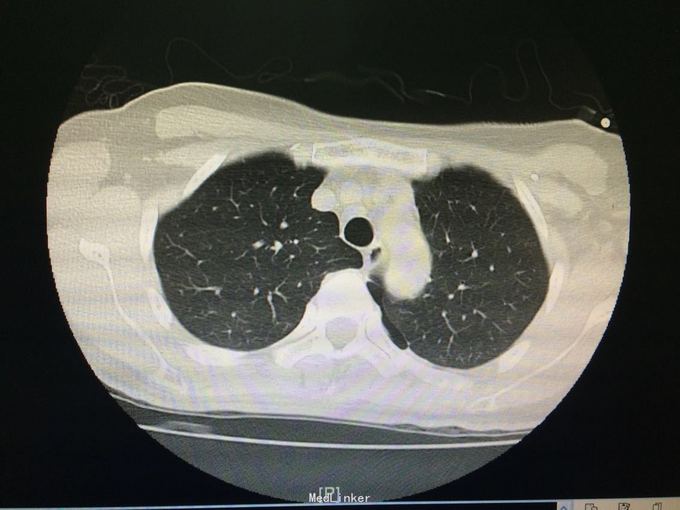

48岁女性,既往高血压。 主诉:咳嗽伴胸痛1周,气促3天。 现病史:1周前无明显诱因出现咳嗽,伴左侧胸壁刺痛,为持续性,活动时加重,休息时缓解。3天前出现气促,一般体力活动后出现,至我院查胸片示:左肺气胸,肺组织压缩约80%,遂入院。

查体:左肺呼吸音明显减弱,右肺正常。双肺未及干湿啰音。 辅查:血常规、凝血、炎性指标等均无明显异常。

诊断:左侧气胸,高血压1级、中危。 入院后予胸腔穿刺加闭式引流排气术,并予头孢咗肟预防感染治疗。负压引流瓶未及气泡冒出、听诊左肺呼吸音明显增强后予夹管复查胸片,示左肺气胸较前好转。